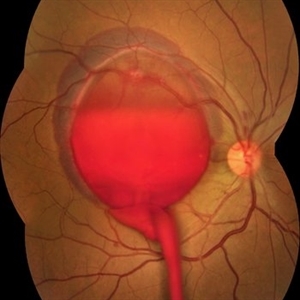

Hamartoma of the Retina

A 4-year-old male patient attended the clinic for evaluation. In the mapping examination and retina and retinography, important alterations were observed in the posterior pole of the left eye. This in turn was sent to perform the ocular ultrasonography examination, which together with the previous examinations, confirmed changes that suggested diagnosis of: COMBINED HAMARTOMA OF RETINA AND PIGMENTARY EPITHELIUM.

Photographer: JEFFERSON R SOUSA - Study Center and Ophthalmological Research Dr. Andre M V Gomes, Institute Dr. Suel Abujamra São Paulo-Brazil

Imaging device: Topcon TRC-50 DX, Imaginet 5.0, angle de 35º . Flash 36 / Mosaic with 9 images.

Condition/keywords: combined hamartoma, retinal pigment epithelium (RPE) hamartoma, tumor